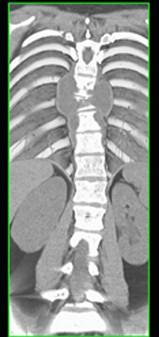

问题 男,34岁,发热,背部疼痛,不能直立,局部软组织肿胀,结合图像,最可能的诊断是 ( )

选项 A、骨肉瘤 B、成骨肉瘤 C、脊柱结核 D、脊柱转移瘤 E、化脓性骨髓炎

答案 E